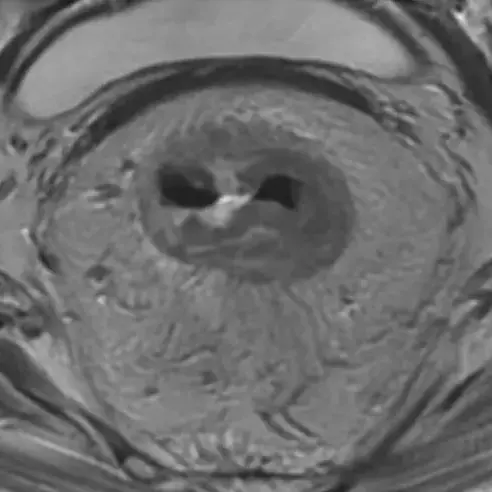

The aim of this work was to investigate the value of rectal cancer T-staging on MRI after chemoradiotherapy (ymrT-staging) in relation to the degree of fibrotic transformation of the tumour bed as assessed using the pathological tumour regression grade (pTRG) of Mandard as a standard of reference.

Twenty two radiologists, including five rectal MRI experts and 17 ’nonexperts‘ (general/abdominal radiologists), evaluated the ymrT stage on the restaging MRIs of 90 rectal cancer patients after chemoradiotherapy. The ymrT stage was compared with the final ypT stage at histopathology; the percentages of correct staging (ymrT = ypT), understaging (ymrT < ypT) and overstaging (ymrT > ypT) were calculated and compared between patients with predominant tumour at histopathology (pTRG4-5) and patients with predominant fibrosis (pTRG1-3). Interobserver agreement (IOA) was computed using Krippendorff’s alpha.

Average ymrT/ypT stage concordance was 48% for the experts and 43% for the nonexperts; ymrT/ypT stage concordance was significantly higher in the pTRG4-5 subgroup (58% vs. 41% for the pTRG1-3 group; p = 0.01), with the best results for the MRI experts. Overstaging was the main source of error, especially in the pTRG1-3 subgroup (average overstaging rate 38%-44% vs. 13%-55% in the pTRG4-5 subgroup). IOA was higher for the expert versus nonexpert readers (α = 0.67 vs. α = 0.39).

ymrT-staging is moderately accurate; accuracy is higher in poorly responding patients with predominant tumour but low in good responders with predominant fibrosis, resulting in significant overstaging. Radiologists should shift their focus from ymrT-staging to detecting gross residual (and progressive) disease, and identifying potential candidates for organ preservation who would benefit from further clinical and endoscopic evaluation to guide final treatment planning.